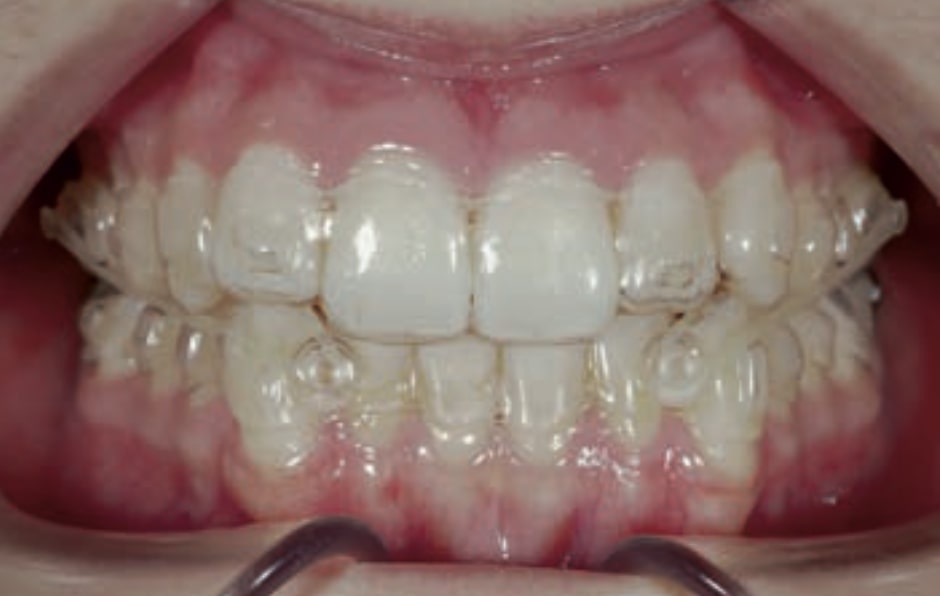

- Distalization of the Third and Fourth Quadrants: Move the teeth distally in these quadrants to achieve a Class I relationship using the A8 protocol, improving the patient’s dental alignment and occlusion.

- Solve the Crossbite of Tooth 33: Correct the position of tooth 33 to eliminate the crossbite, contributing to a more balanced occlusion.

- Intrusion of the Lower Anterior Teeth: Adjust the vertical position of the lower anterior teeth to level the curve of Spee, improving the harmony of the occlusion.

Treatment setup

Treatment progress